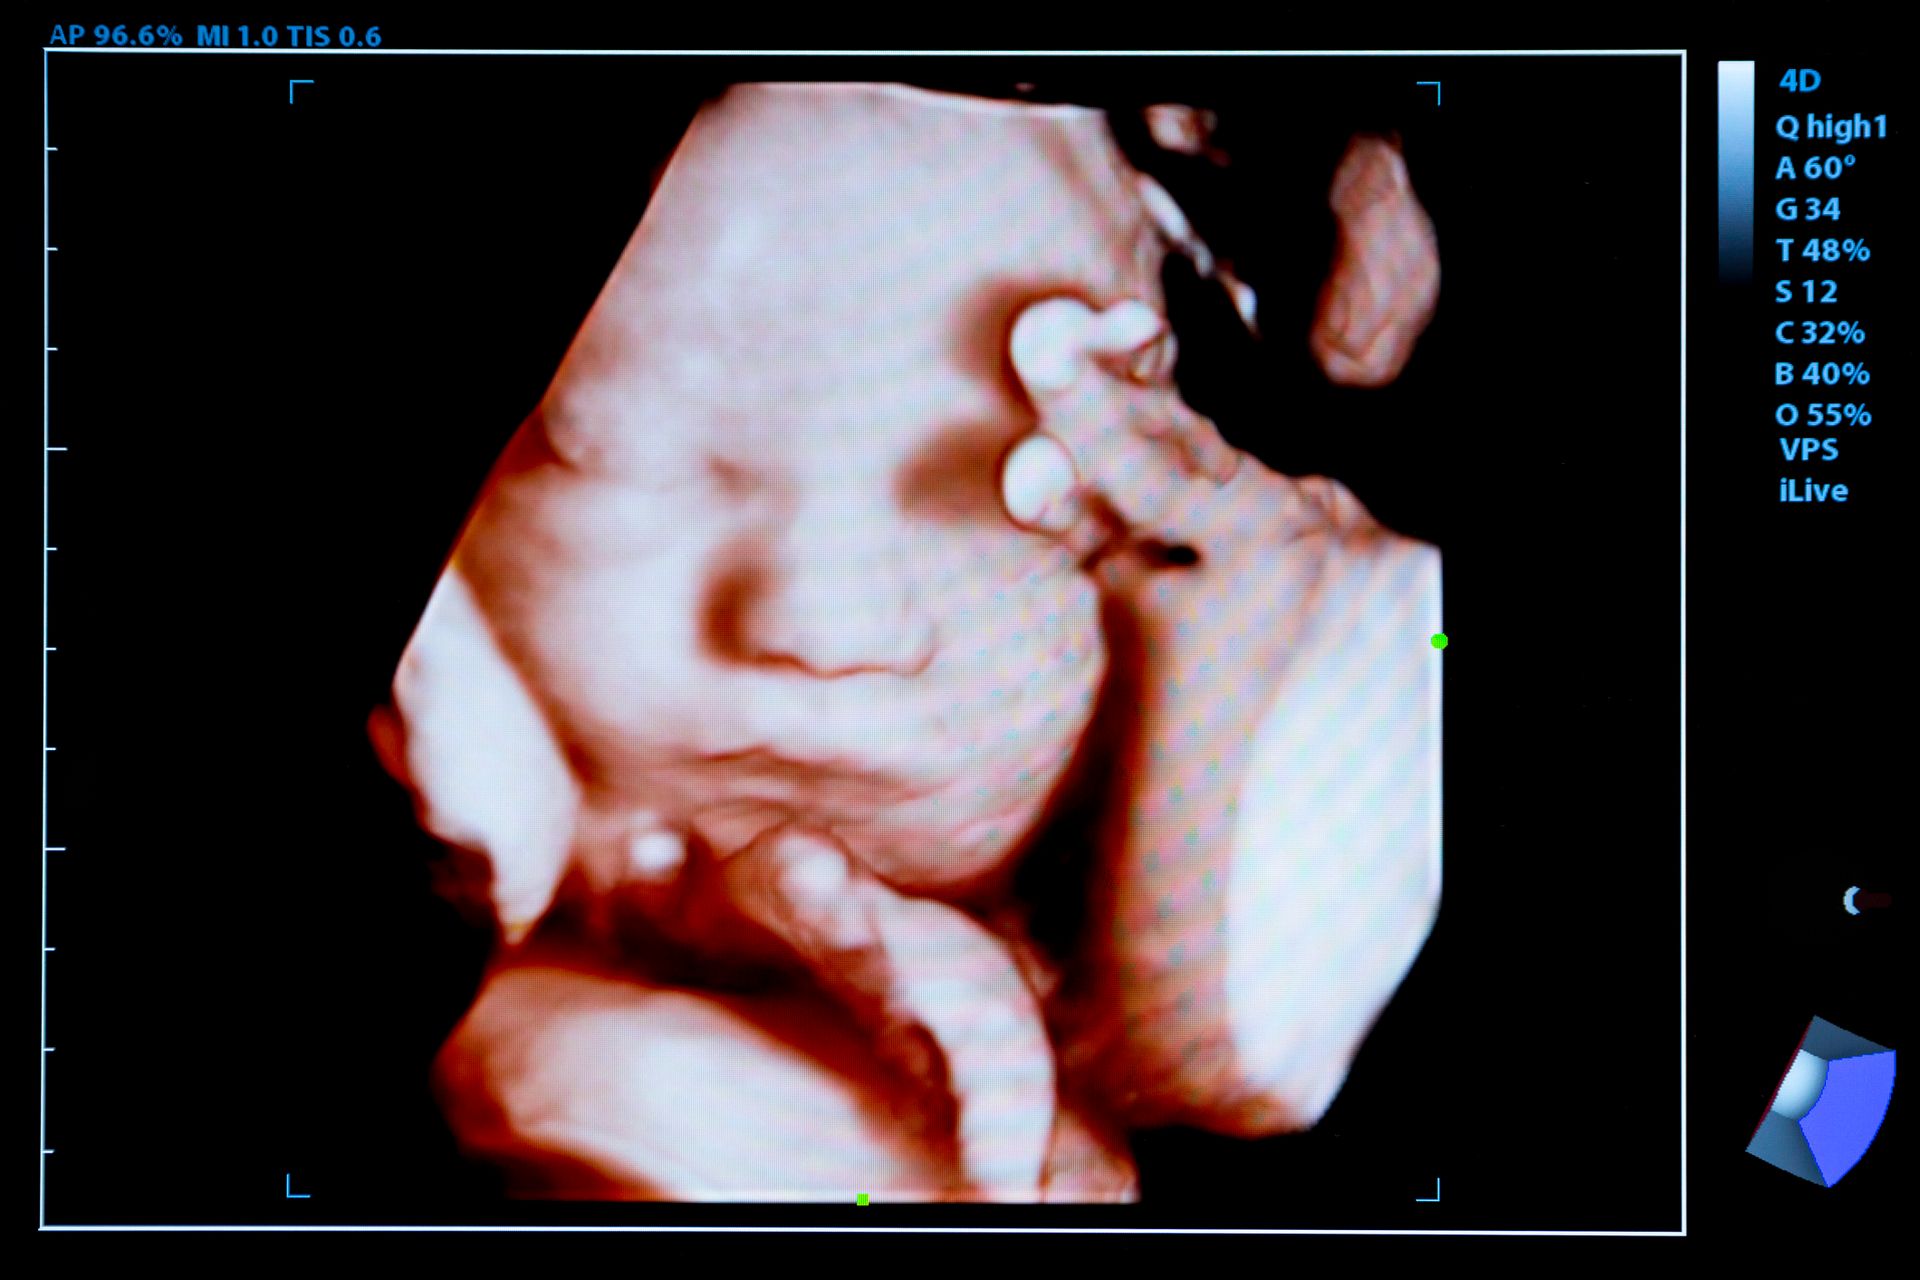

Diagnosi ecografica, ostetrica prenatale, ecografia ginecologica, chirurgia mini invasiva del basso tratto genitale femminile.